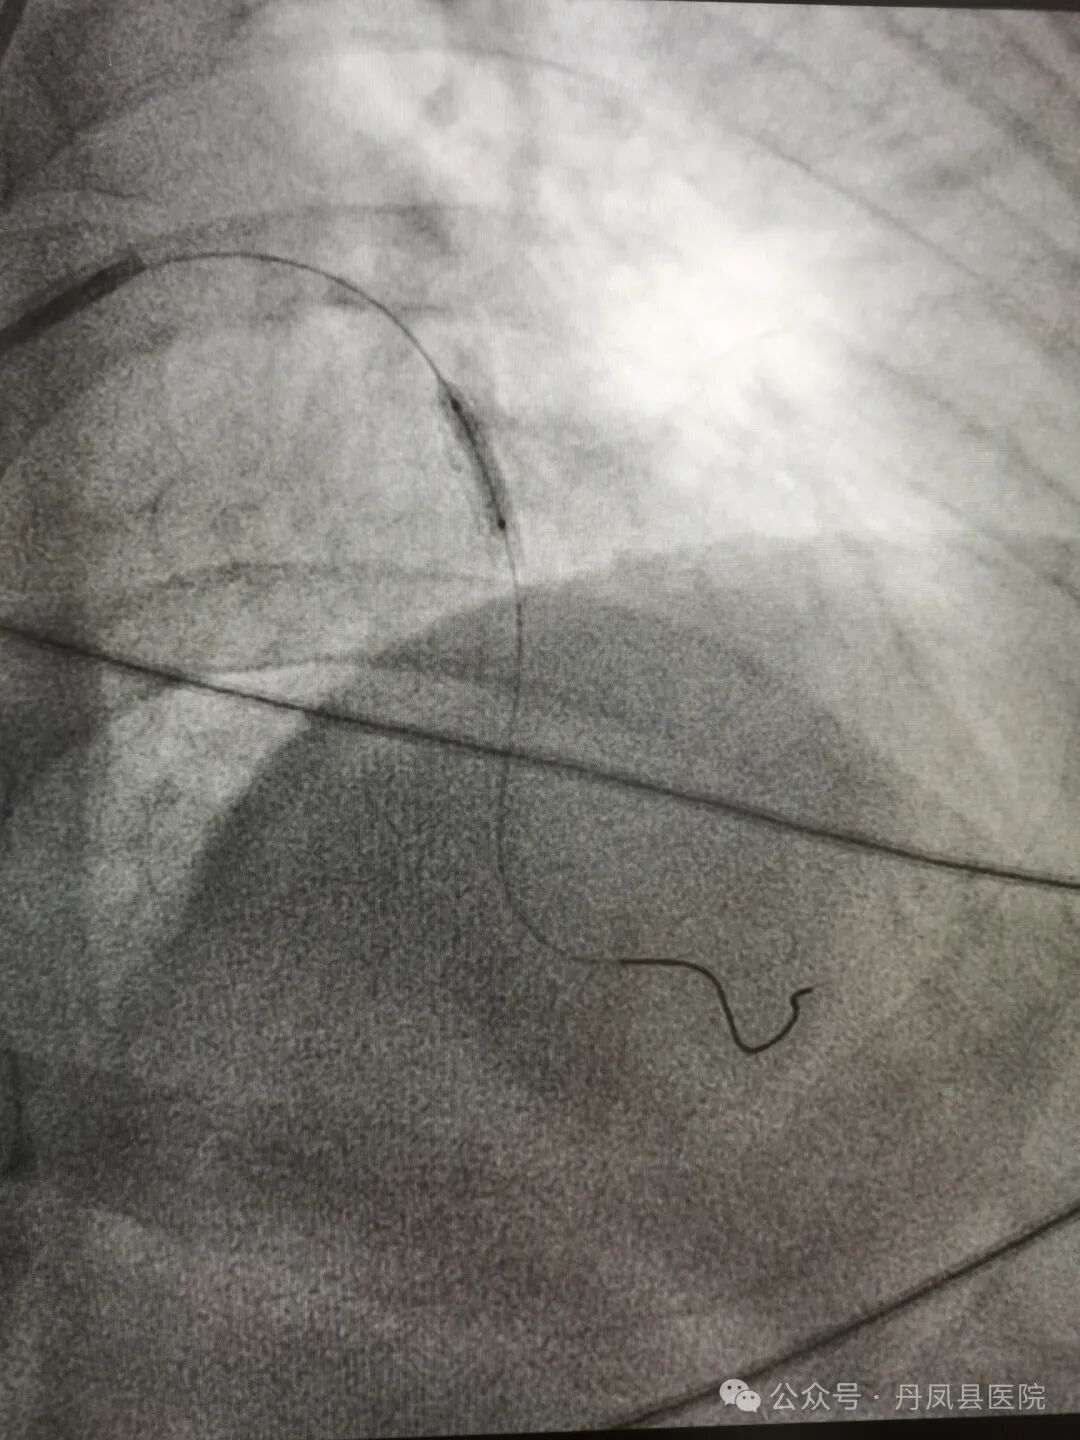

图1、图2为造影下发现病变,图3为术中球囊释放,图4为球囊释放后。